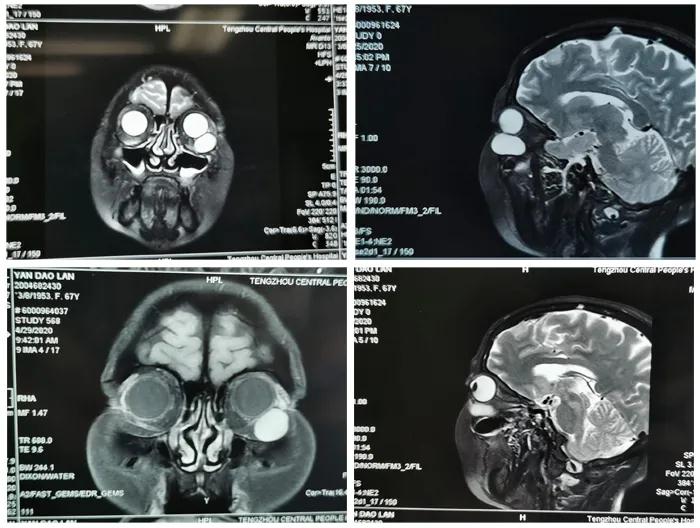

患者,女,65歲。因“發(fā)現(xiàn)左眼眶內(nèi)腫物3月”于5月24日收入眼二科病房。入院行眼眶CT、MRI檢查,術(shù)前閱片發(fā)現(xiàn)該患者左眼眶內(nèi)腫物,體積大,位置較深,邊界清,直徑約3.0cm類圓型腫物,與下直肌有粘連。